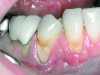

The presence of keratinized tissue around teeth and implants and its role in periodontal maintenance is somewhat controversial. It has been suggested that 2 mm of keratinized tissue is important to maintain gingival health around teeth.16 Minimal recession also facilitates maintenance by the therapist and plaque control by the patient (Figure 4 and Figure 5). Keratinized tissue around implants is also important. Chung et al17 completed a retrospective study examining the barrier function of keratinized tissue around dental implants. They examined 339 endosseous dental implants in place for at least 3 years in 69 patients and found that when an adequate band of keratinized tissue was present, less inflammation and plaque accumulation occurred (Figure 6 and Figure 7). Although there was no correlation to bone loss, there was improved comfort while cleaning the sites with keratinized tissue versus those areas that lacked keratinized tissue.

Fig 4. Severe recession visible on teeth Nos. 29 and 30.

Figure 4

Fig 5. Teeth Nos. 29 and 30 following connective tissue grafting showing minimal recession and improved tissue health.

Figure 5